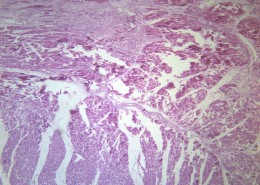

风湿性心肌炎(12)张

心肌炎指心肌中有局限性或弥漫性的急性、亚急性或慢性的炎性病变。近年来病毒性心肌炎的相对发病率不断增加。病情轻重不同,表现差异很大,婴幼儿病情多较重,成年人多较轻,轻者可无明显病状,重者可并发严重心律失常,心功能不全甚至猝死。急性期或亚急性期心肌炎病的前驱症状,病人可有发热、疲乏、多汗、心慌、气急、心前区闷痛等。检查可见期前收缩、传导阻滞等心律失常。谷草转氨酶、肌酸磷酸激酶增高,血沉增快。心电图、X线检查有助于诊断。治疗包括静养,改进心肌营养、控制心功能不全与纠正心律失常,防止继发感染等。